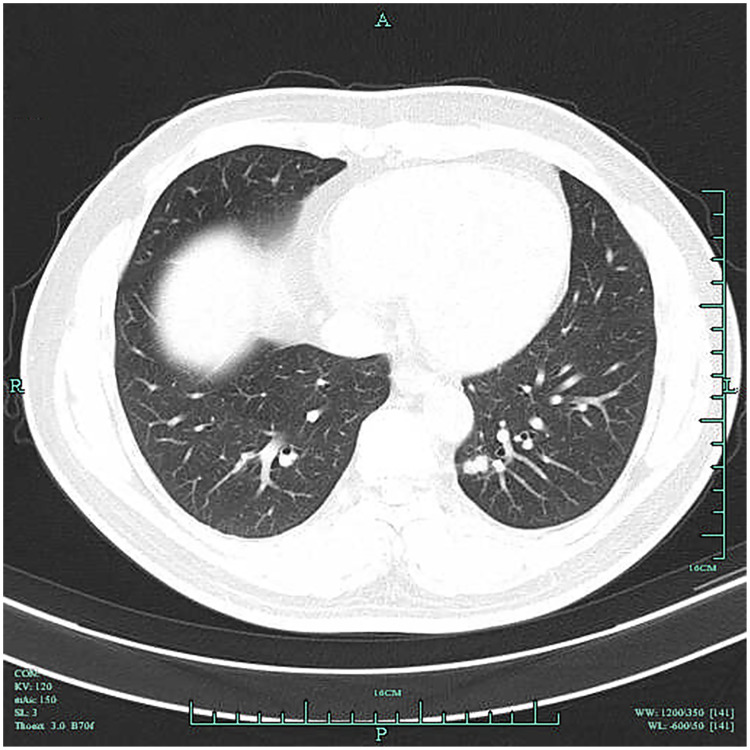

Purpose: Early detection of lung cancer is critical to improving prognosis, yet current screening methods such as low-dose spiral CT and serum CEA each have diagnostic limitations. This study aims to analyze the clinical value of low-dose spiral CT combined with serum CEA in the differential diagnosis of early lung cancer.

Materials and methods: In this retrospective study, 62 patients diagnosed with early lung cancer in our hospital from April 2022 to October 2023 were selected as the case group, and 50 patients diagnosed with benign pulmonary lesions during the same period were selected as the control group. Data from low-dose spiral CT and serum CEA levels were compared. The efficacy of low-dose spiral CT alone, serum CEA alone, and the combination of both in discriminating early lung cancer was assessed using ROC curves.

Results: Low-dose spiral CT showed a sensitivity of 77.42%, a specificity of 94.00%, and an AUC of 0.8571 (95% CI: 0.7832-0.9310) in detecting early lung cancer. Serum CEA levels were significantly higher in the case group compared to the control group (P<0.05). Serum CEA yielded an AUC of 0.8661 (95% CI: 0.7964-0.9359) in distinguishing early lung cancer (P<0.0001). Low-dose spiral CT combined with serum CEA detection achieved an AUC of 0.9137 (95% CI: 0.8624-0.9650), significantly increasing the early lung cancer detection rate from 82.26% to 95.16% (P<0.05).

Conclusion: Patients with early lung cancer show distinct alterations in low-dose spiral CT signs, and their serum CEA levels demonstrate a notable increase compared with those with benign pulmonary lesions. The combination of low-dose spiral CT with serum CEA can be considered in the discrimination of early lung cancer, which can markedly enhance the positive detection rate while maintaining a minimal rise in false-positive rates.